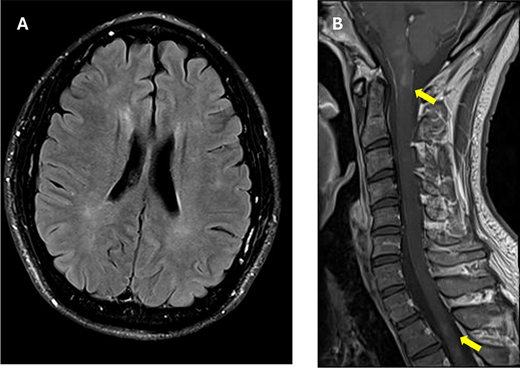

The patient’s magnetic resonance imaging (MRI) at 10 months after the seizure onset. He had intermittent paresthesia in the left leg, and his reflexes were increased in his right arm and leg. A, Axial fluid-attenuated inversion recovery (FLAIR) imaging of the brain shows ill-defined hyperintense lesions in the periventricular regions. B, Sagittal T1-weighted image of the spinal cord shows new short hyperintense lesions affecting the brainstem, the cervical spinal cord, and upper thoracic spinal cord (arrows).

In May 2024, MRI revealed new subcortical enhancing lesions, despite the absence of symptoms. By November 2024, the patient developed intermittent paresthesia in the left leg and right-sided hyperreflexia. Imaging demonstrated progressive lesions in the brainstem and cervical spine. Neurological examination remained largely normal, apart from hyperreflexia and mild sensory disturbances. Despite extensive testing for infectious and autoimmune etiologies, no alternate causes were identified. Repeated corticosteroid therapy provided symptom relief. The relapsing-remitting radiological course was consistent with an ADEM/MOGAD spectrum diagnosis, and the patient was planned to receive rituximab.